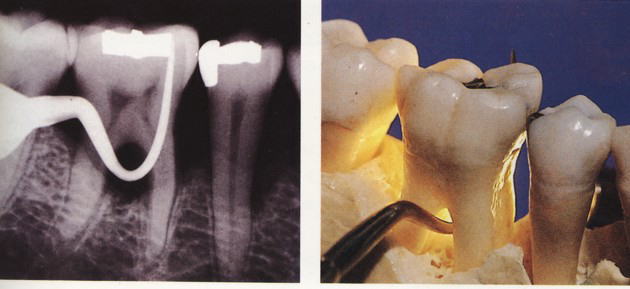

『ラ タイチャークの図版』より

多くの場合は歯周病の一つの病形で、歯周病一般の原因と同様、歯に付着した細菌性プラーク(デンタルバイオフィルム)によって惹き起こされる炎症性の感染症です。辺縁歯肉(ポケットの元の形である歯肉嚢の入り口)のブラッシングが不十分であったためプラークが形成され、歯根面を覆っていた歯槽骨が次第に吸収され、歯根分岐部が歯肉の中で露出している様態にあります。 2 根分岐部病変の症状

根分岐部病変が一旦発症してしまうと、その治療はなかなか困難です。多くの場合大臼歯部で起こるため、その位置的な事情や歯根の懈怠の複雑さなどから、正確な診断、術者側の施術、患者さんの管理などいずれも困難を極めます。

治療法としては様態に応じて、スケーリング・ルートプレーニング・分岐部入り口の整形によって磨きやすい形態を作る→歯槽骨の整形→歯根に対する処置(いずれかの根を抜歯する・複数の根の間を分割するなど)やトンネルの形成などの処置があります。 また「再生療法」として薄い皮膜を用いて歯槽骨の再生を誘導する『組織再生誘導法(GTR法)』や特殊な薬剤を用いる『エムドゲイン法』などがあります。 |